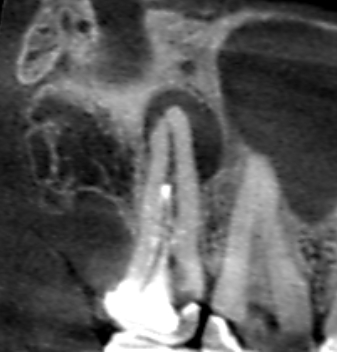

Vol.29 根の先と根の分岐部の両方に膿がみられたケース

上顎第一大臼歯の根の先と根の分岐部の両方に膿がみられたケースです。他の歯の根管治療でCTを撮影し…

上顎第一大臼歯の近心根に膿がみられました。実は、Vol.37、Vol.38、Vol.39は同じ患者さ…